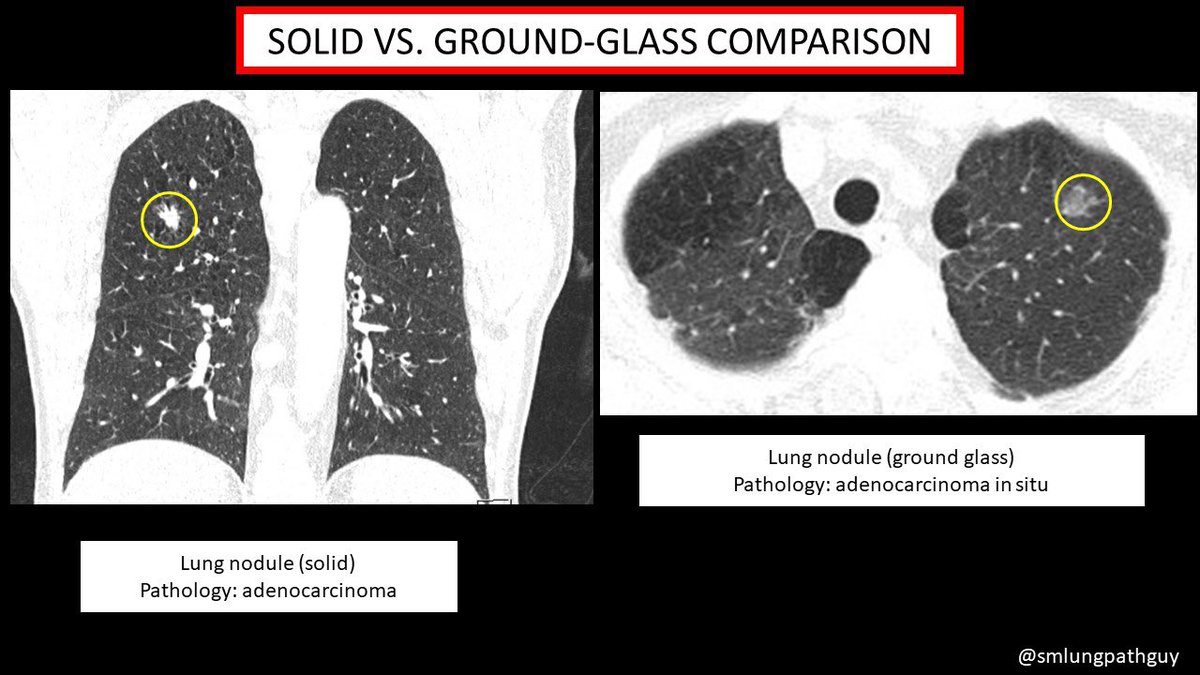

I made these slides to explain ground-glass opacities and ground-glass lung nodules to my medical students and residents. Please feel free to use them to teach yours. 🙏🏾 #pathology #pulmpath #radpath #imaging Howard Mann Tan-Lucien Mohammed, MD, FACR Leticia Kawano-Dourado (I'm on BlueSky/LinkedIn)